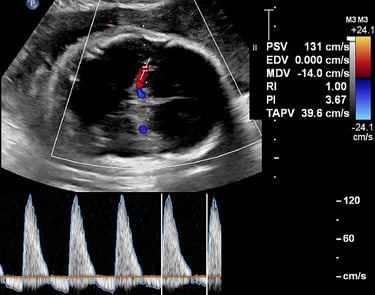

As scanning proceeds, color, power, and spectral Doppler are introduced where they add diagnostic value, not just technical complexity. Learners repeatedly practice fetal cardiac and vascular assessments, placenta and cord evaluation, and biophysical profile techniques in context.